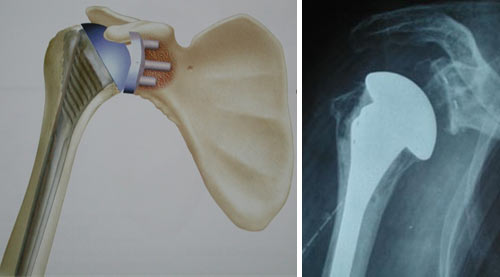

* Les prothèses totales d'épaule anatomique remplacent artificiellement la totalité de l'articulation de l'épaule : humérus ET glène de la scapula.

Elles comportent un composant en général métallique fixé dans l'humérus et un composant glénoïdien souvent en plastique. Elles sont indiquées principalement dans l'arthrose et les nécroses avancées avec atteinte de la glène.